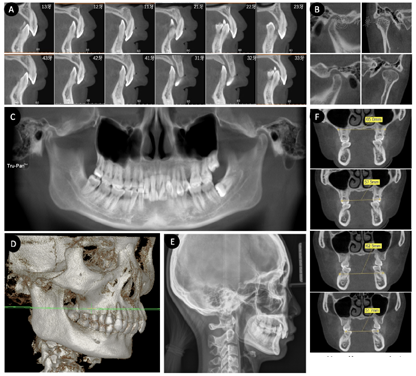

口外检查:正面观显示面部基本对称,面下1/3较短;侧面观显示低角,上下唇稍突与E-Line前方,鼻唇角正常,颏唇沟深。双侧关节运动检查显示双侧开闭口无明显的弹响/杂音/疼痛,开口型无明显偏斜(图1)。

口内检查:矢状向显示上下前牙明显舌倾,双侧尖牙为远中关系,双侧磨牙中性偏远中;垂直向显示重度深覆合,Spee曲线深度右侧12 mm左侧8 mm;水平向显示上下方圆形牙弓,上牙弓宽大/下牙弓窄小,24牙25牙与对颌牙形成正锁合,左下后牙明显舌倾;上牙列中度牙列拥挤,下牙列重度牙列拥挤,上中线基本居中,Bolton指数前牙比76.5%/全牙比81.1%。25牙变色,近中邻牙合在龋,探已穿髓,探痛(-),扣(-)。口腔卫生尚可,软垢少许,下牙舌侧少牙石。部分牙龈红肿,探出血,BI1-4,PD2-6mm。下前牙牙龈退缩,根面暴露至根中1/2~根尖1/3,松动I~Ⅱ°。上前牙部分牙角化龈不足,牙根唇倾明显,根形明显(图1)。

影像学检查:CBCT显示25根尖区阴影,上下前牙牙槽骨吸收至根颈1/3-根尖1/3,下前牙唇侧严重牙槽骨缺损,上前牙唇侧大面积骨开窗。颞下颌关节检查显示双侧髁状突大小形态不一致,关节前间隙较大后间隙较小,髁状突处于关节窝的后位,但表面皮质骨平滑延续。CT三维重建直观显示患者的深覆合致上颌合曲线显著异常,上前牙唇侧大面积骨开窗。头影测量分析显示SNA角77.5°,SNB角72.3°,ANB角5.2°,FH-MP角20°,OP-FH角5.2°,U1-L1角171.2°,U1-SN角64.6°,L1-MP角76.9°,Wits值6.7 mm,U1-PP距32.3 mm,U6-PP距21.2 mm,L1-MP距41.9 mm,L6-MP距28.4 mm。CBCT上下颌骨冠状向显示上下颌骨宽度稍异常而牙弓宽度明显异常,上牙弓较宽而下牙弓较为窄小(图2)。